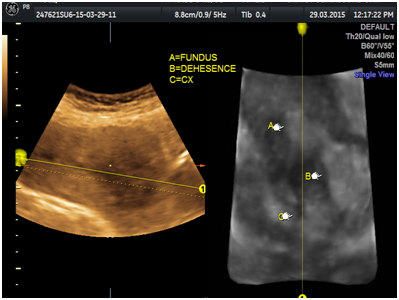

A 29-year-old multiparous woman at 11weeks’ gestation was referred to our hospital for termination of pregnancy due to suspected placenta accreta or cesarean scar ectopic by abnormal vasculature around lower uterine segment gestational sac on ultrasound. She had delivered 2male children by cesarean section. The patient underwent ultrasound due to complain of vaginal bleeding. It revealed lower uterine segment pregnancy with abnormal vasculature in the placenta bed suspicious of placenta accreta or cesarean scar ectopic pregnancy about 10weeks gestation (Figure 1). The decision was done to evacuate the pregnancy vaginally by surgical means. The patient underwent surgical evacuation under ultrasound guidance but severe vaginal bleeding occurred. The procedure was ended and uterovaginal packing was done for 24hrs. The patient was vitally stable. The procedure was performed transabdominal ultrasound examination after 24hrs that revealed bulky uterus with hematoma inside cavity and there was a defect (3cm×2.0cm) in the lower anterior uterine wall with no fluid collection in the abdomen (Figures 2-5). The patient was vitally stable with no vaginal bleeding. We removed the vaginal pack intraoperative under general anesthesia, prepared for laparotomy in case of severe bleeding. No bleeding occurred, the patient discharged after 1 week and follow-up after one month revealed normal uterus.

Figure 1 lower uterine segment with abnormal vasculature in placenta bed suspicious of early placenta accreta or cesarean scar ectopic pregnancy.

Figure 2 Transabdominal ultrasound revealing hematoma in the lower uterine segment after evacuation.

Figure 3Transabdominal ultrasound revealing defect in the lower anterior wall on 3D view.